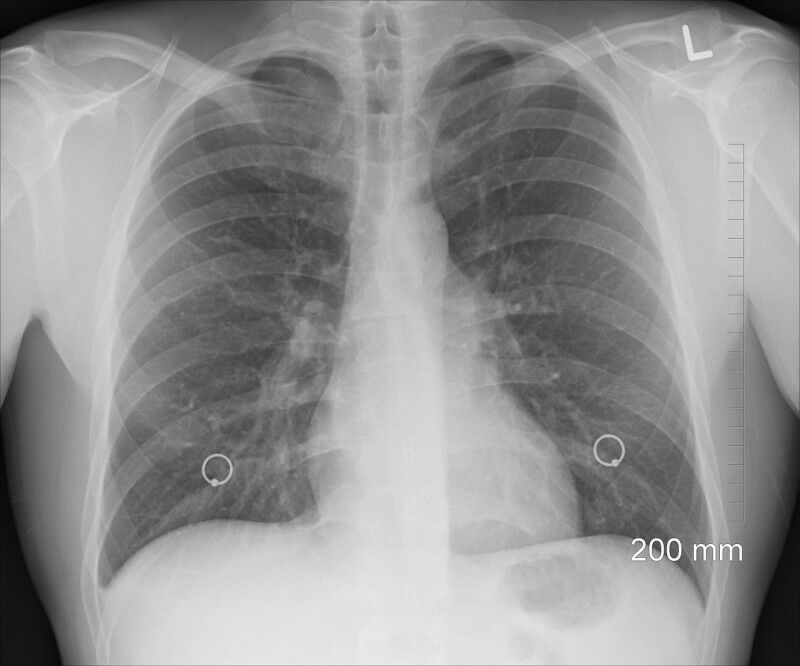

(Image: Pixabay CC0) - Small cell lung cancer (SCLC) is a particularly aggressive tumour, which has so far been treated with standardised measures. A study led by MedUni Vienna has shown for the first time that different SCLC subtypes have specific molecular characteristics, which is why those affected respond in different ways to cancer treatment. This discovery, published in the Clinical and Translational Medicine journal, has opened up new options for the development of more personalised treatment for this cancer, which is characterised by an unusually high rate of mortality. Earlier this year, a study by an international team of scientists led by MedUni Vienna indicated that small cell lung cancer (SCLC) is not a homogeneous type of cancer but is rather characterised by four subtypes that respond differently to treatment measures. The researchers from Austria, Hungary, Brazil, Sweden and the Netherlands are highlighting that a single treatment method for SCLC is not effective with their current follow-up project. Rather, the results of their comprehensive analyses provide the basis for new treatment approaches that can be tailored to the specific molecular characteristics of the respective subtypes. Specific Proteins for Targeted Treatment - In order to generate these results, the scientists analysed the entire protein composition (proteome landscape) of human SCLC cell lines.